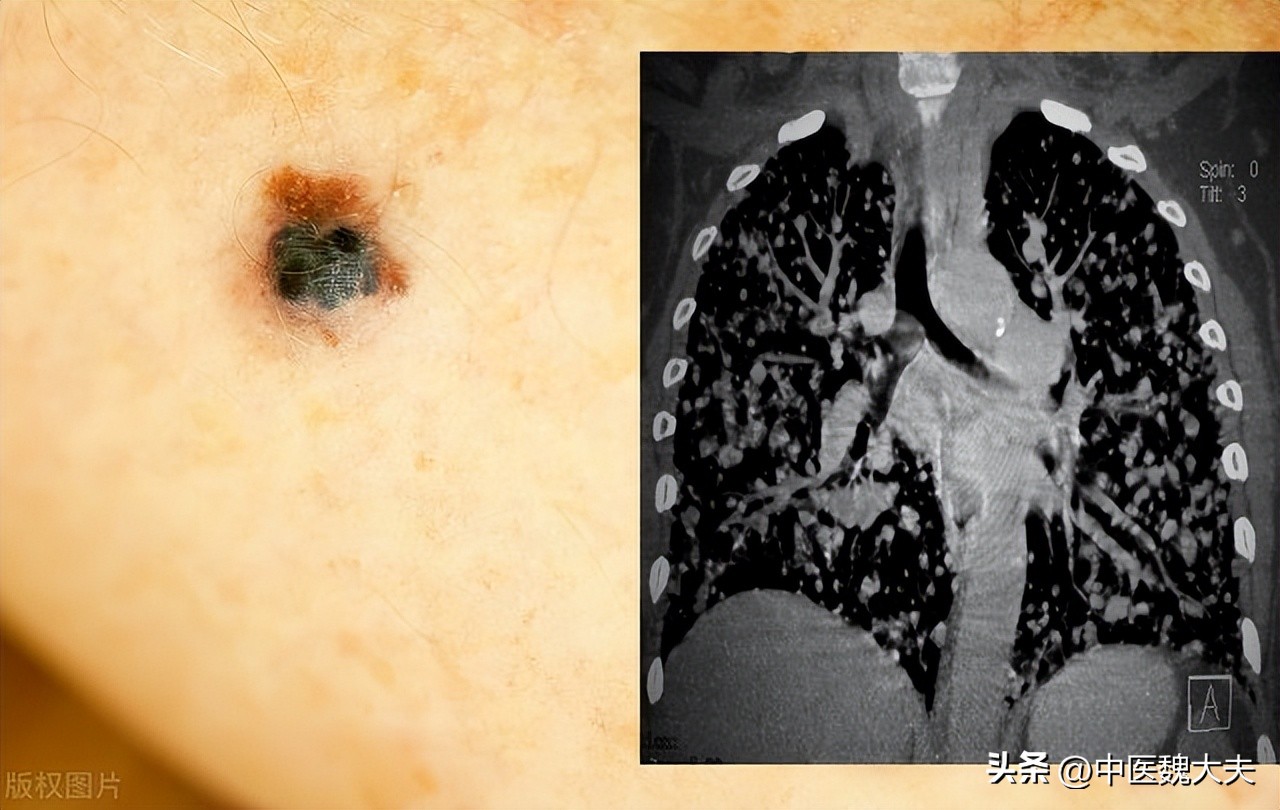

小张偶然发现自己皮肤上长了一颗很奇怪的痣,这颗痣不像其他黑痣那样形状规则,而是一边大一边小,颜色也是一些地方深,一些地方浅。一开始小张也没当回事,可是这颗痣越长越大,有时还会发痒流血,和家人说了后,家里人都说没事,于是小张也就没放在心上。

毕业工作后,小张在一次常规体检时,医生发现了这颗不同寻常的痣,医生建议他去做个详细的检查。结果,检查出来竟是黑色素瘤,由于耽误了很久才确诊,病情已经发展到很严重的程度了,目前已扩散到淋巴结。

小张一开始很难接受这个事实,但还是积极配合了治疗,通过手术将黑色素瘤切除,可过了10个月后,黑色素瘤又继续扩散到了肺部,出现了咳嗽、咯血等症状。

另外,黑色素瘤和普通的黑痣在形状、大小、颜色等方面上也会有所不同,可以通过以下5这个方面去分辨:

1、形状不规则:可能会出现一边偏大一边偏小;

2、边缘不规则:普通的黑痣边缘是比较清晰而且整齐的,而黑色素瘤的边缘一般有锯齿痕迹,边缘不整齐与周围皮肤分界不清;

3、颜色不均匀:颜色分布的不均匀,可能存在多种颜色;

4、直径:黑色素瘤比普通黑痣要大,直径会超过6毫米;

5、其它:在最近几周或几个月时间里,痣发生了比较明显的变化,比如突然的变大、颜色或形状发生了改变,早期的黑色素瘤可能会出现轻微的隆起,或者出现瘙痒出血。